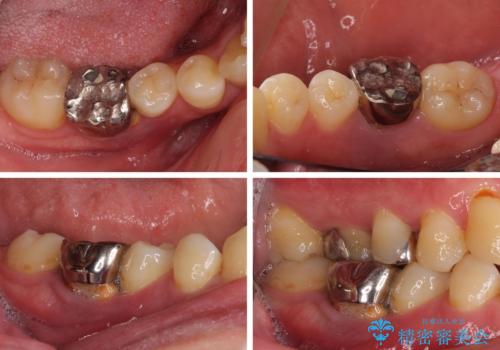

左右下顎の大臼歯は、ともに歯根が破折しており、抜歯が必要な状態でした。

放置したことで炎症による骨吸収が顕著であるため、骨造成を併用してインプラント埋入を行うこととしました。